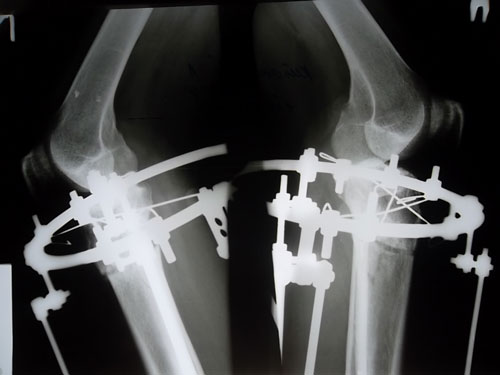

90 дней с момента операции.

Рентгеновские снимки.

Сращение отличное, Ваша подвижность и подготовка к ремонту, пошла Вам на пользу! :lol:

Вложения

SAM_5589.JPG

SAM_5592.JPG